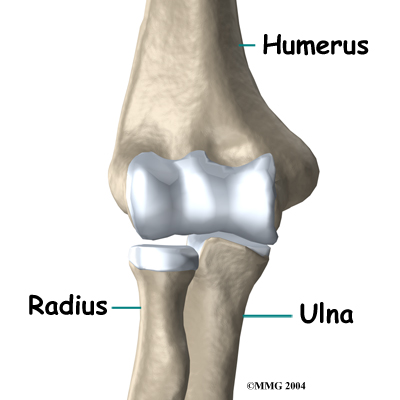

The elbow is the connection of the upper arm bone (the humerus) and the two bones of the forearm (the ulna and the radius). The radius runs from the outer edge of the elbow down the forearm to the thumb side of the wrist.

The joint where the humerus meets the radius is called the humeroradial joint. This joint comprises a bony knob and a shallow cup. The knob on the end of the humerus is called the capitellum. The capitellum fits into the cup-shaped end of the radius. This cup is called the head of the radius.

When the head of the radius spins on the capitellum, the forearm rotates to turn the palm up toward the ceiling (supination) or down toward the floor (pronation). The joint also hinges as the elbow bends and straightens.